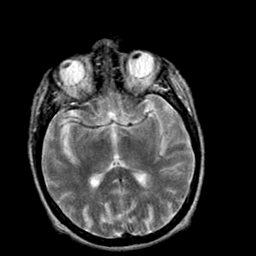

Creutzfeld-Jakob disease: T2-weighted MR -- Slice #11

[Home][Help][Clinical] Slice 11